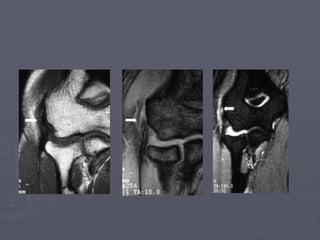

►RNM demonstra espessamento do tendão

com aumento de sinais

►USG: fluido subjacente ao tendão,laceração

e microrrupturas